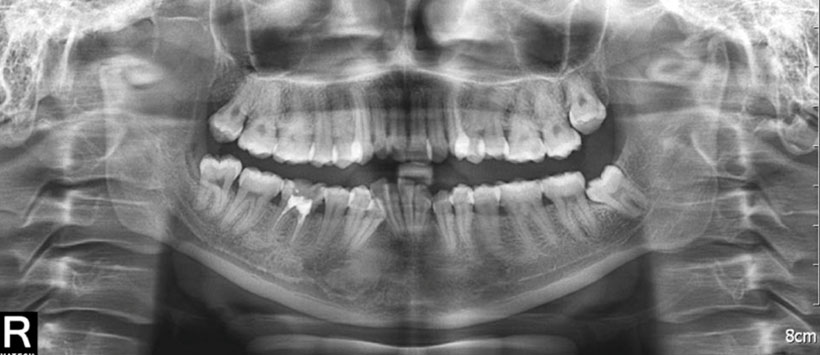

Figura 1: Radiografía panorámica que muestra morfología asimétrica del cóndilo mandibular derecho con borde irregulares en zona posterior (flecha negra) y una pequeña imagen radiopaca de densidad cálcica en forma de masa (flecha blanca).

Figura 4: Radiografía panorámica que muestra cóndilo mandibular irregular con ensanchamiento del espacio articular del lado derecho.

Figura 6: Radiografía panorámica que muestra posiciones asimétricas de ambos cóndilos mandibulares, sin otro mayor hallazgo.